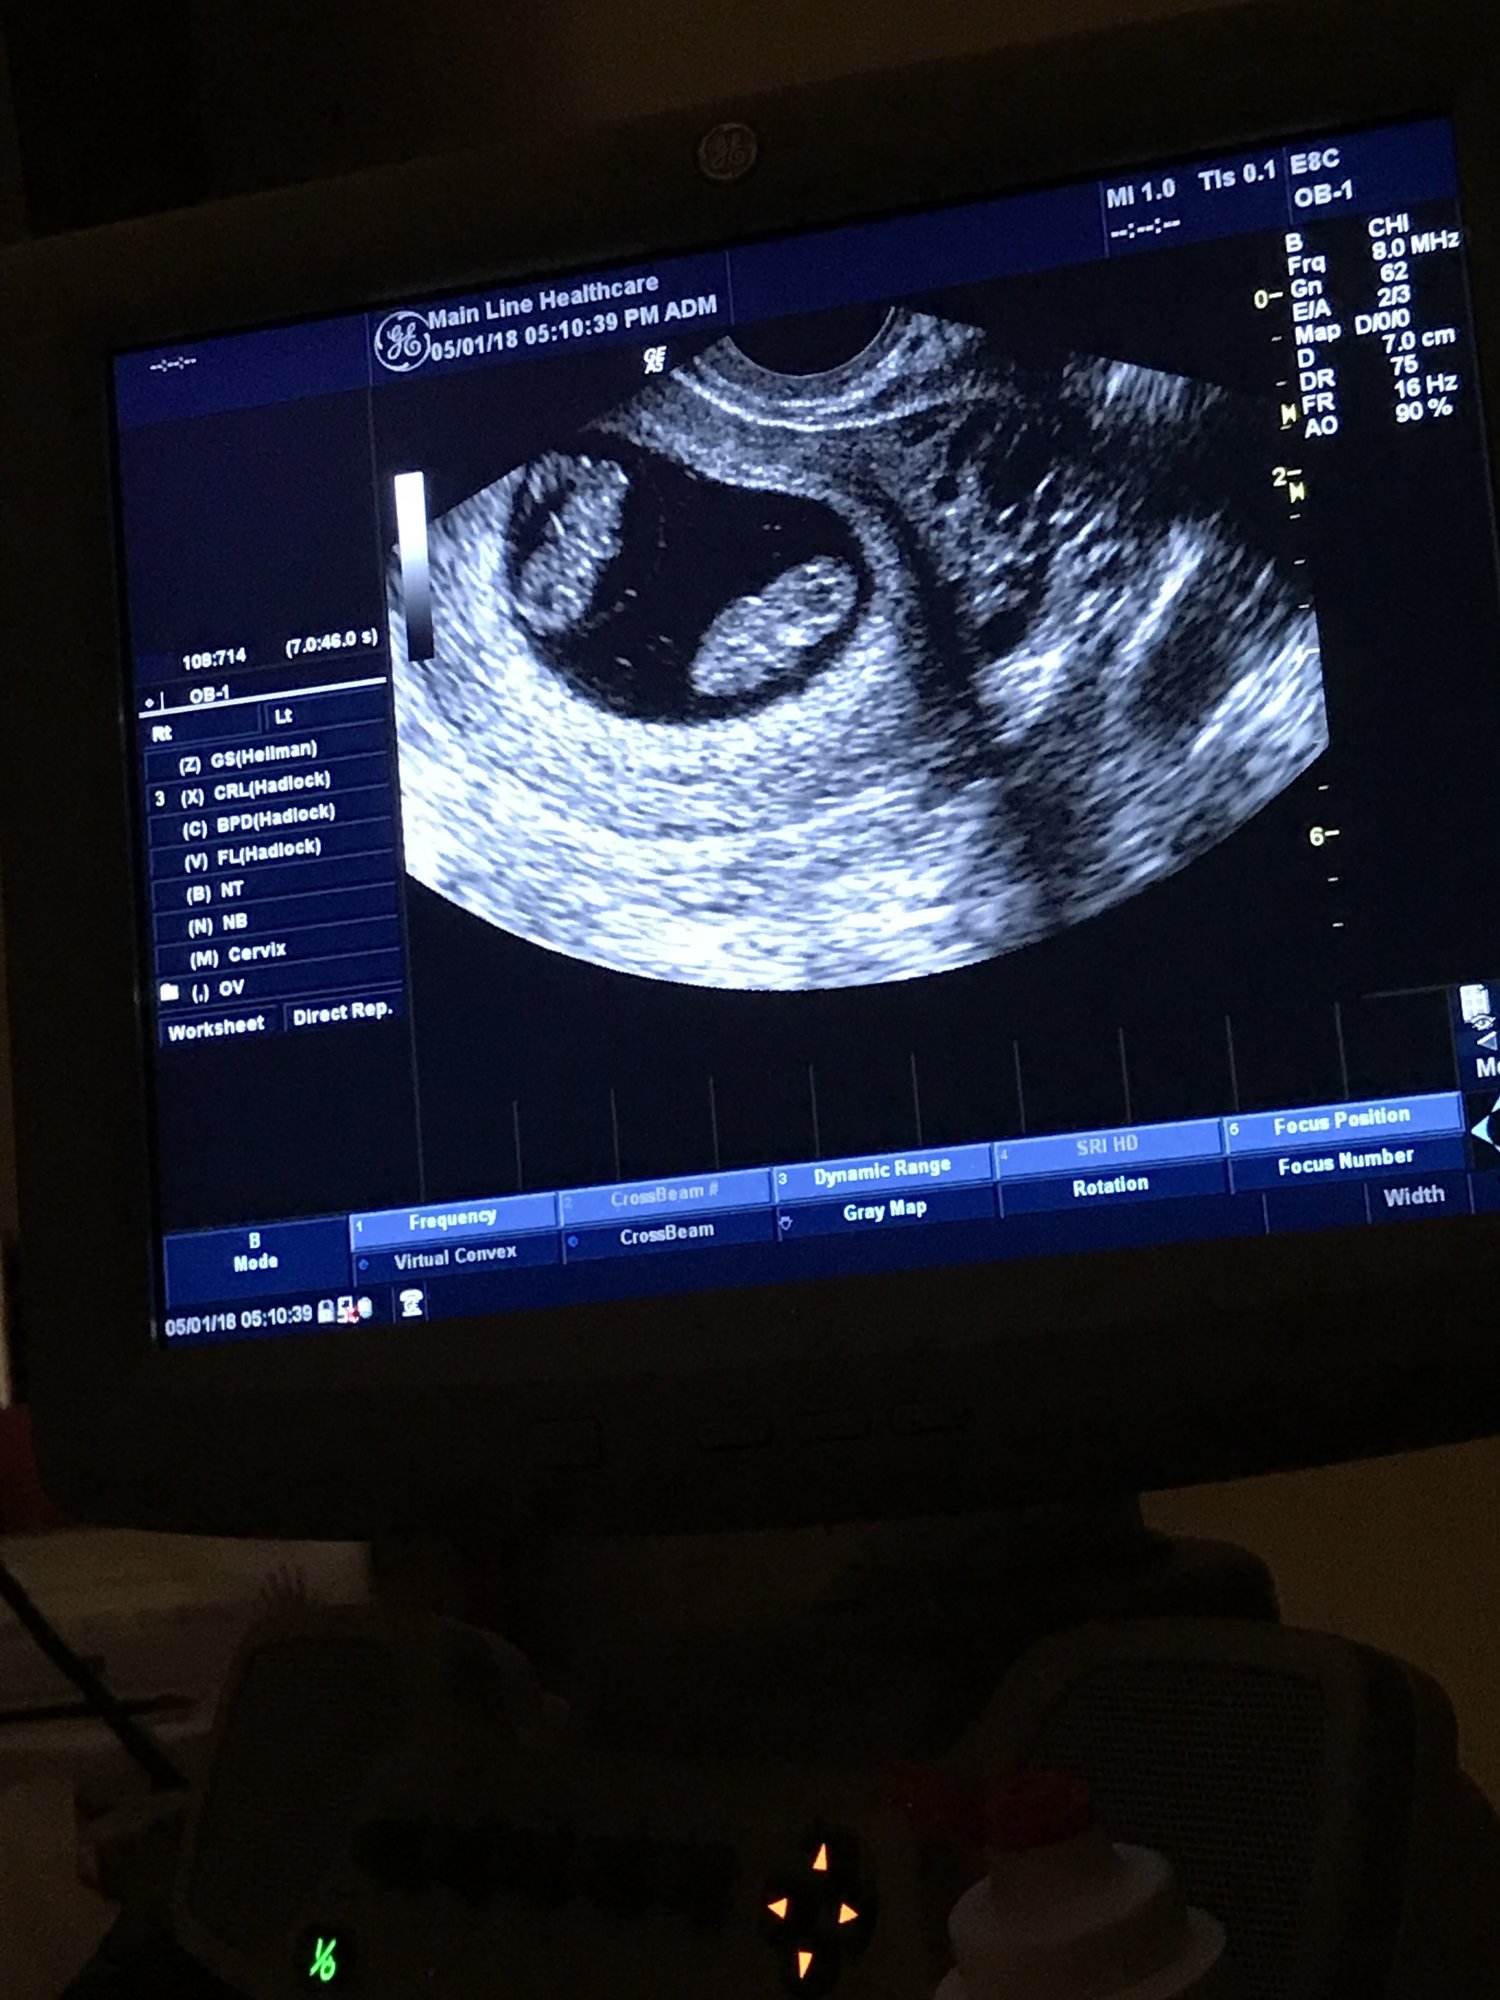

Our little one was 10w 2d at the US, I am now 11w 1d! We have a wiggle worm! He/she was all over the place! HR 170. Love this baby so much already and feeling so blessed! Due 11/27!